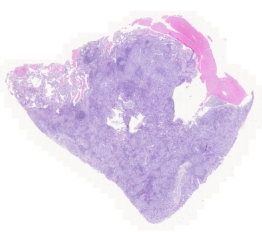

To handle aforementioned challenges, we propose a deep learning pipeline combined with weakly supervised learning. This pipeline is a step towards ushering inexpensive and timely tumor detection, histological subtyping, and mutation identification. We present our findings from developing convolution neural networks (CNNs) for such tasks based on TCGA WSIs from the US as well as an Indian dataset from the Tata Memorial Centre (TMC) in Mumbai. The work on TMC data was approved by the TMC Institutional Ethics Committee. These datasets contain gigapixel sized WSIs of formalin-fixed paraffin embedded (FFPE) tissue sections that are stained using inexpensive and ubiquitous H&E stains and scanned at magnification. Figure1 shows some snapshots of slides from both datasets.

Our pipeline is based on several practical considerations. Firstly, to handle large size of WSIs, we segmented the tissue region of each WSI. Then we extracted patches from the segmented tissue of each WSI. We found a huge colors variations among extracted patches. This variation is due to staining protocols, habit of technician, reagent brands and color response of scanner. To mitigate this variation, we performed color normalization on extracted patches as shown in Figure 4. All the color normalised tissue patches of each WSI served as input to the CNN to create a set of low-dimensional feature embedding (Figure 4). Low-dimensional feature spaces are more suitable for faster training and reduced computational cost. By projecting patches to a low-dimensional space, the volume of data is reduced nearly 200 times and led to subsequent reduction of computational requirements to train deep learning models. These embeddings were used for all three tasks – tumor detection, histological subtyping, and EGFR mutation prediction. Since visual features associated with the mutation cannot be reliably annotated by a pathologist, a weakly supervised learning technique was used for the third task. At a high-level during training and inference both, the model examines and ranks all patches in the tissue regions of WSI for their relevance in EGFR mutation prediction. An attention score is assigned to each patch on the basis of importance or contribution to the collective slide-level representation for a particular class. This attention score is used for the slide-level aggregation based on attention-based pooling, which computes the slide-level representation as the average of all patches weighted by their respective attention score, as shown in Figure 4.